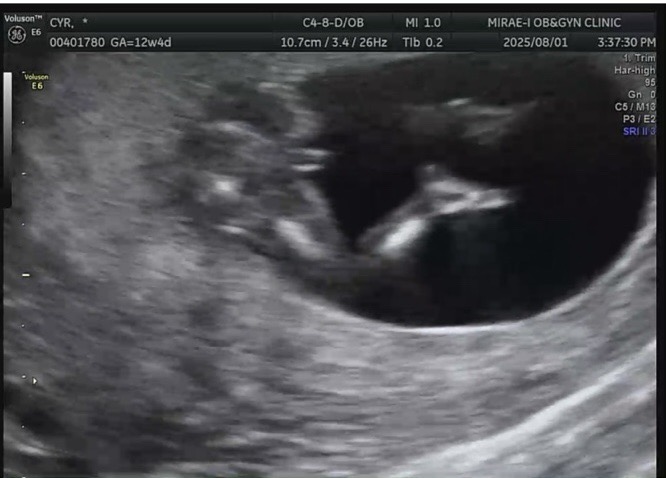

각도법 봐주실 전문가쌤 계신가요~?

의사선생님은 모양은 딸인데 크기가 아들같다고 하시더라구요..! 성별 상관없긴한데 그래도 궁금하긴 하네요ㅎㅎ